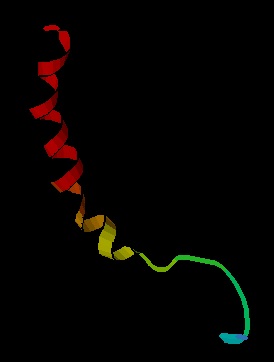

191. Jahnichen S NMR solution structure of Neuropeptide Y. http://en.wikipedia.org/wiki/File:Neuropeptide_Y.png .

191a. Monks SA Karagianis G Howlett GJ Notrton RS Solution structure of human neuropeptide Y J. Biomol NMR 1996 Dec; 8(4):  379-390.